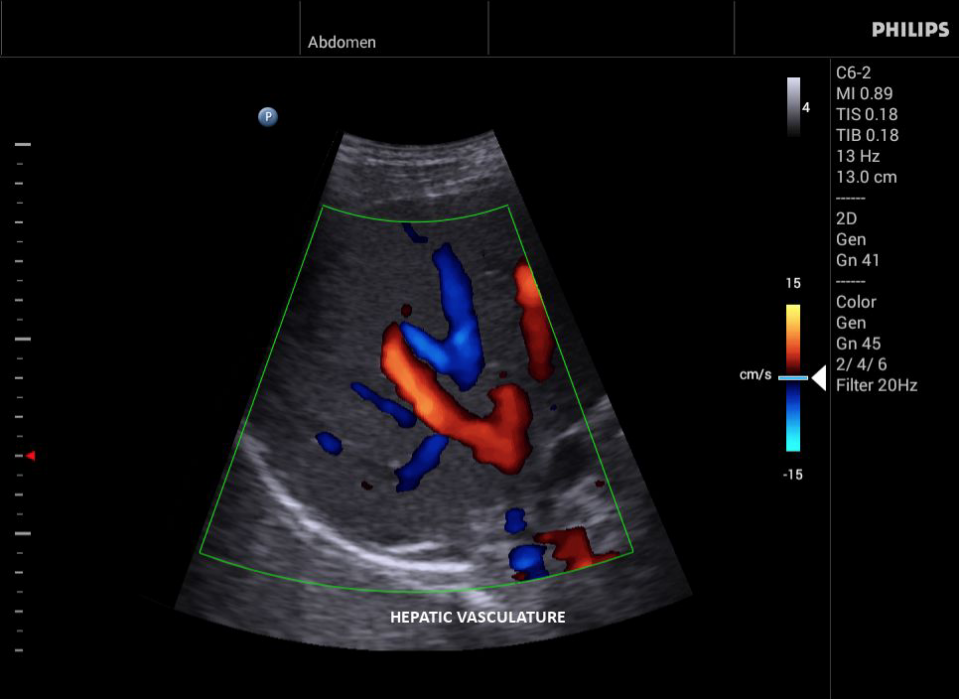

УЗИ-аппарат

Philips InnoSight

Philips InnoSight увеличивает возможности сканирования во множестве мест оказания медицинских услуг. Благодаря данному УЗИ аппарату врачи могут не сомневаться в быстром выполнении обычных ультразвуковых сканирований во врачебном кабинете, клинике или больнице.

InnoSight позволяет перенести ультразвуковую диагностику непосредственно туда, где пациенту оказывается медицинская помощь, что повышает мобильность врачей. Этот компактный и легкий ультразвуковой аппарат позволяет чаще использовать возможности ультразвуковой диагностики и предоставляет широкий набор технологий для проведения углубленных исследований — программные пакеты для специализированного анализа, функции аннотирования и наборы готовых настроек для различных типов тканей.

Эргономичная система с высококачественными широкополосными датчиками Philips помогает повысить клиническую надежность результатов исследования и уровень оказания медицинских услуг. Аппарат можно перемещать вручную или с помощью тележки.

• Исследования сосудов;

• Дуплексный режим: Одновременное отображение режимов 2D и допплера.

• Триплексный режим: Одновременное отображение режимов 2D, допплера и цветного допплера или энергетического допплера.

• Цветное допплеровское картирование

• Направленный энергетический допплеровский режим: Дополнительно к возможностям визуализации сосудов в стандартном энергетическом режиме добавляется информация о направлении. Этот режим полезен для визуализации мелких сосудов в качестве замены цветного допплеровского картирования.